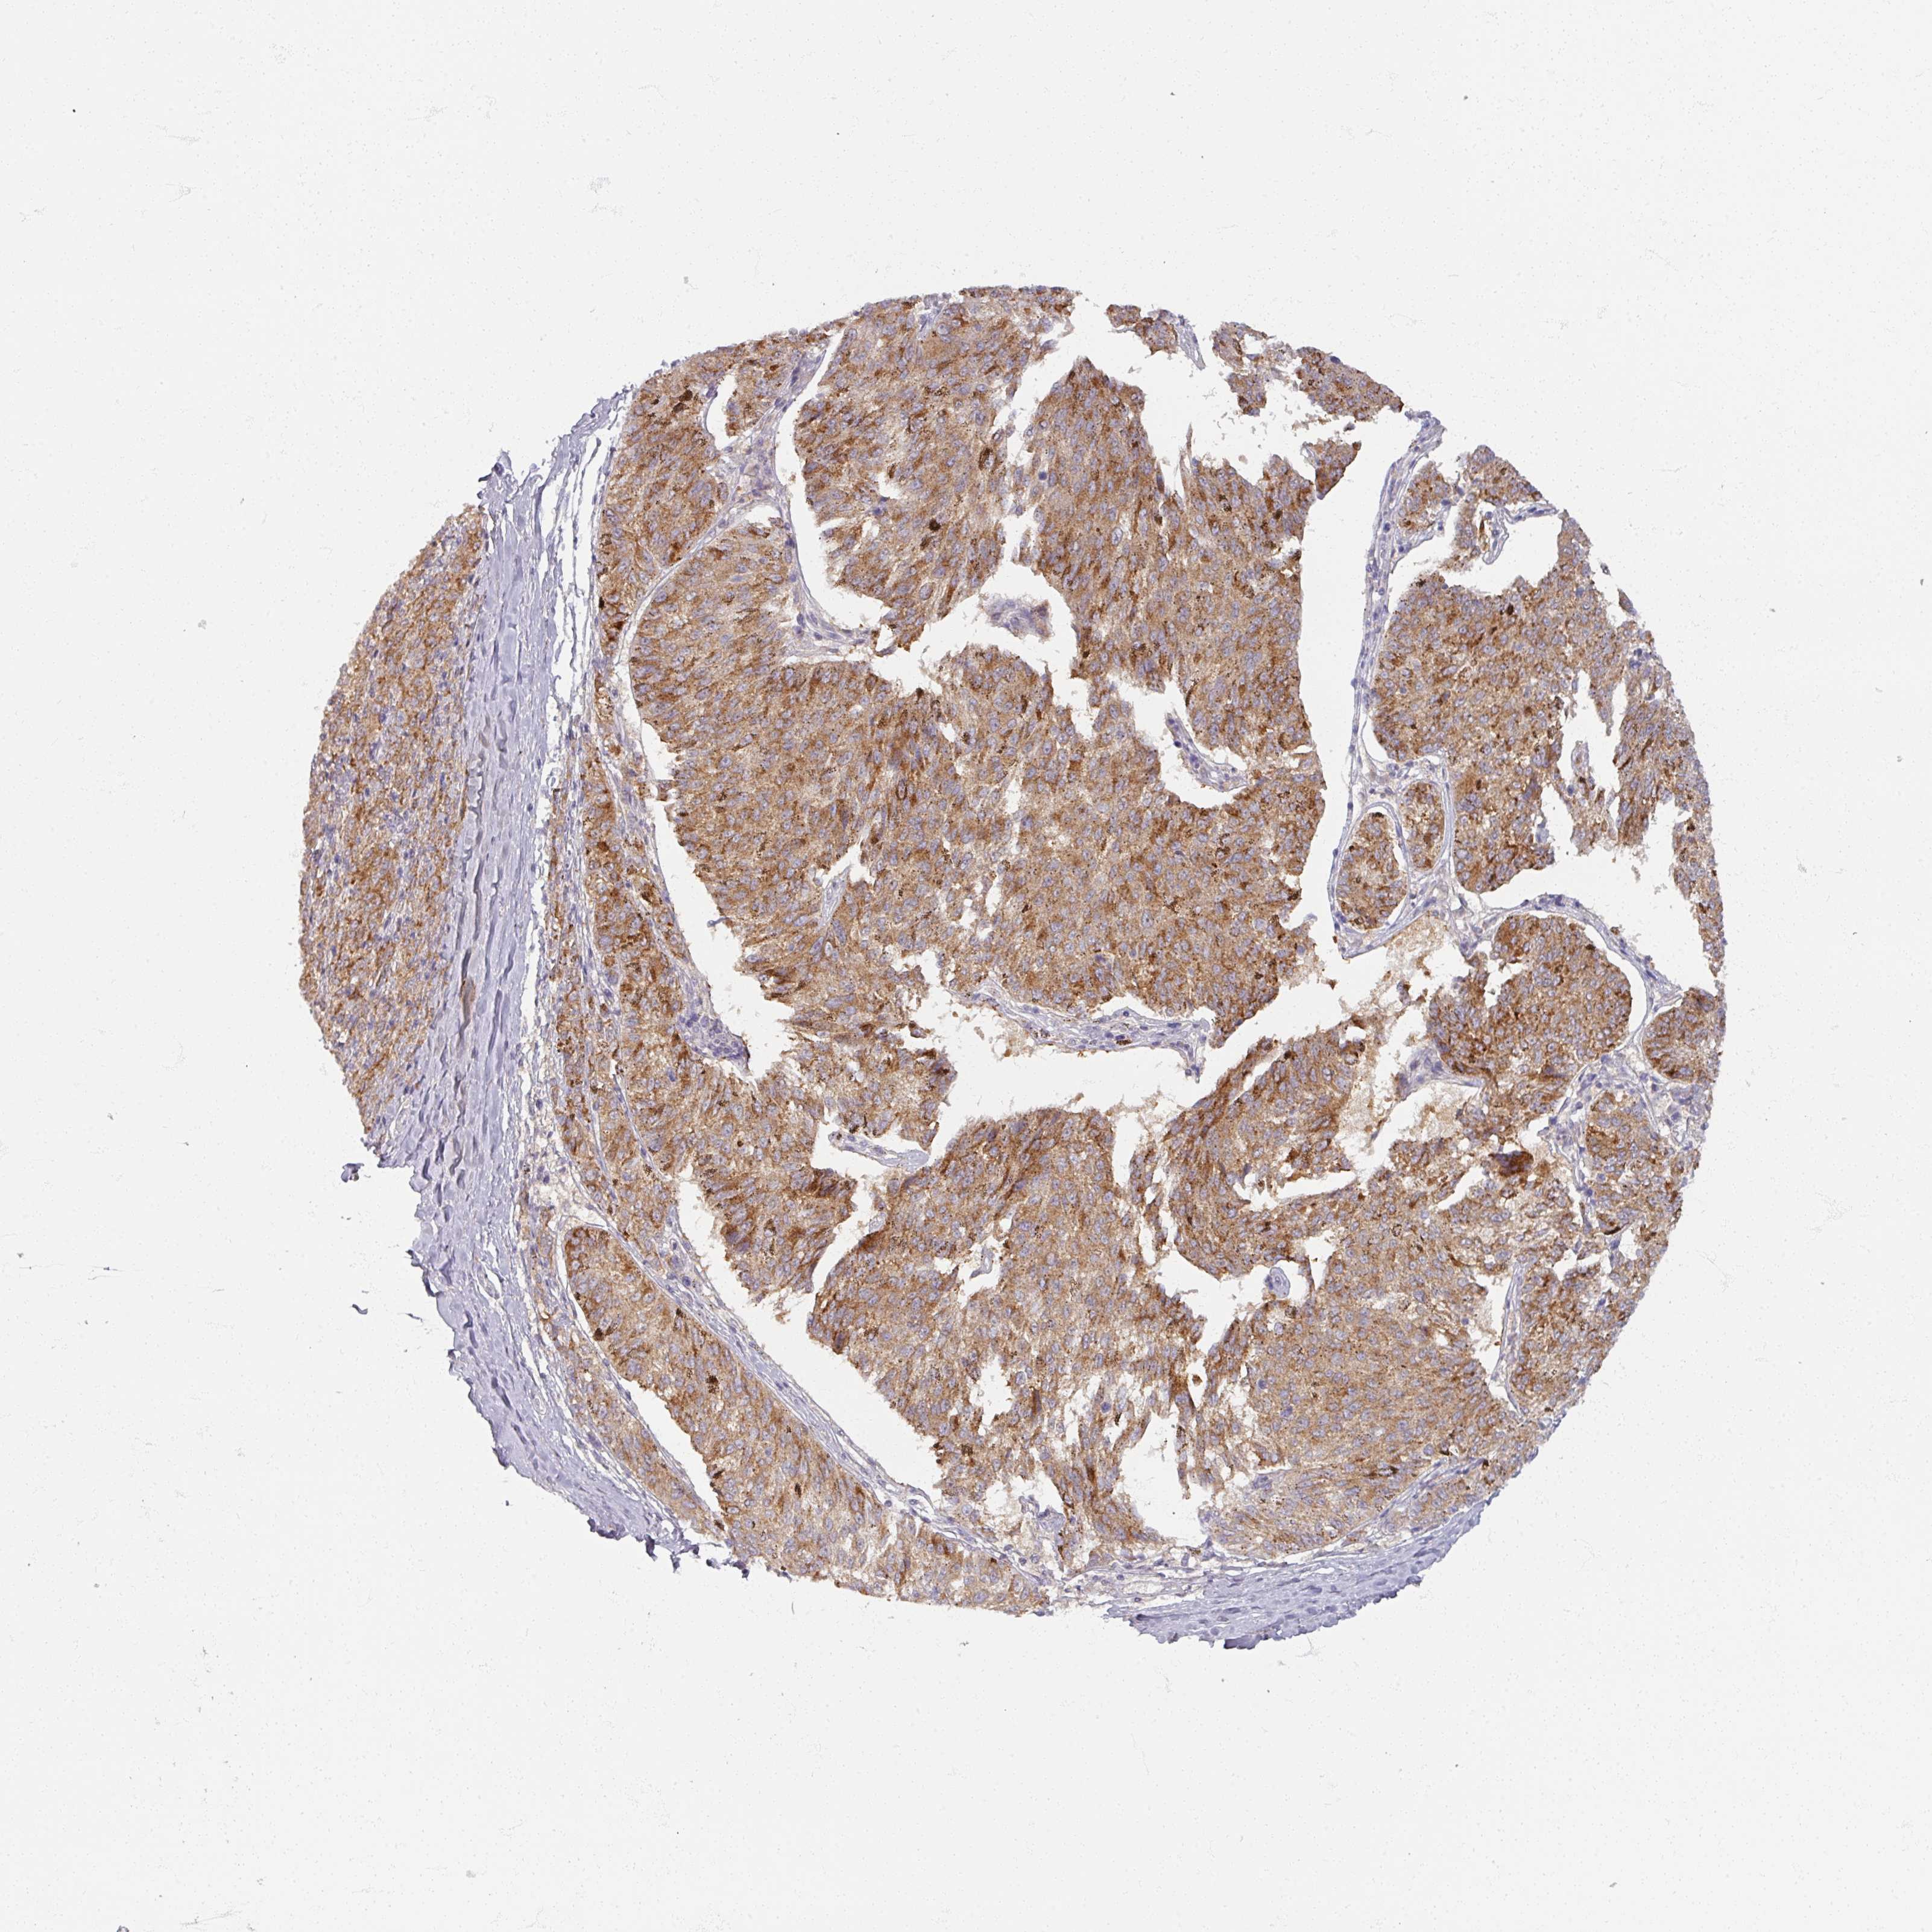

MELANOMA - Protein expressioni

A mouse-over function shows sample information and annotation data. Click on an image to view it in a full screen mode. Samples can be filtered based on level of antibody staining by selecting one or several of the following categories: high, medium, low and not detected. The assay and annotation is described here.

Note that samples used for immunohistochemistry by the Human Protein Atlas do not correspond to samples in the TCGA dataset.

Antibody stainingi

Antibody staining in the annotated cell types in the current human tissue is reported as not detected, low, medium, or high, based on conventional immunohistochemistry profiling in selected tissues. This score is based on the combination of the staining intensity and fraction of stained cells.

Each image is clickable and will lead to virtual microscopy that enables deeper exploration of all samples and also displays staining intensity scores, fraction scores and subcellular localization as well as patient and tissue information for each sample.

Antibody HPA000536

Antibody CAB056152

Antibody CAB056153

Staining

High

Medium

Low

Not detected

Intensity

Strong

Moderate

Weak

Negative

Quantity

>75%

75%-25%

<25%

None

Location

Nuclear

Cytoplasmic/membranous

Cytoplasmic/membranous,nuclear

Malignant melanoma, NOS

Malignant melanoma, Metastatic site